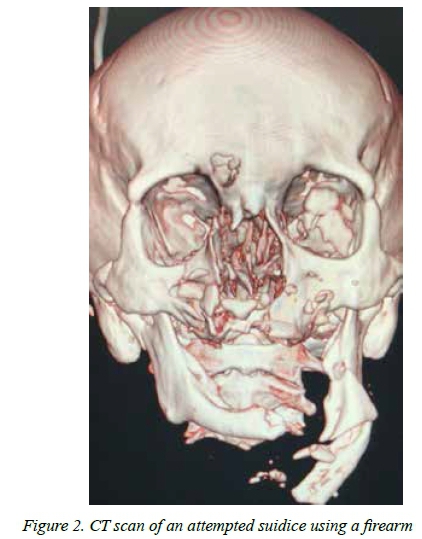

The mechanism was penetrating trauma in 47 (26%). The penetrating mechanisms included stab wounds (SW) in 33, gunshot wounds (GSW) in 10, broken glass in 2 and a single impalement. Figure 1 shows a self-inflicted wound of the neck and Figure 2 shows the CT scan of a suicide victim who attempted to shoot himself in the head. Blunt mechanisms accounted for the remaining 131 (73%) injuries. The most common mechanism of blunt self-harm was hanging in 101 patients. This was followed by vehicular related trauma in (8), jumping in front of a train in (1) and jumping from a height in (1). In 17 patients, the exact mechanism of the blunt trauma was unclear. There was no statistical difference in the mechanism of injury between male and female patients. There were 38 (28%) men and 9 (23%) women who sustained a penetrating injury and there were 100 (72%) male and 31 (78%) female patients who had a blunt mechanism of injury. Table 3 summarizes the mechanisms of injury according to sex.

A total of 53 CT scans were obtained, 40 chest X-rays, 9 abdominal X-rays and 2 ultrasounds. Table 4 tabulates these investigations. There were 113 neck injuries, 68 head injuries, 24 abdominal injuries, 15 upper limb and 15 lower limb injuries and four facial injuries. A total of 32 operations were performed. These included laparotomy (14), neck exploration (5), and tracheostomy (4). The remainder are listed in Table 5. A total of 22 patients developed a complication. These are broken down in Table 5. A total of 4.5% of patients required ICU admission and the overall mortality rate was 2.5%. Figure 1 demonstrates a self-inflicted laceration of the neck in an acutely psychotic patient. This required a neck exploration and ligation of a severed internal jugular vein and reconstruction of the injured larynx. Figure 2 is the CT scan of a man who shot himself in the face. He survived the injury and required extensive reconstructive surgery.

Self-harm related injuries place a significant burden on all departments in the hospital. They often require imaging and not infrequently require surgical treatment. The most common operations are laparotomies and neck explorations. Occasionally significant injuries require complex surgical reconstruction involving a number of sub-specialties. The man with the laceration to his neck (Figure 1) required complex reconstruction and a tracheostomy whilst the patient with the gunshot wound to his face (Figure 2) required complex plastic and maxillofacial surgery.